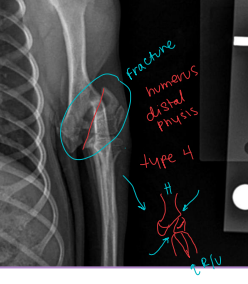

Salter-Harris = Physeal Fractures

Common in young animals (open physes)

Condylar Fractures: Lateral > medial

Sig: Young dogs w/ Salter-Harris IV, older dogs w/ incomplete ossification of humeral condyle

Tx:

Lateral condyle: lag screw + anti-rotational K-wire